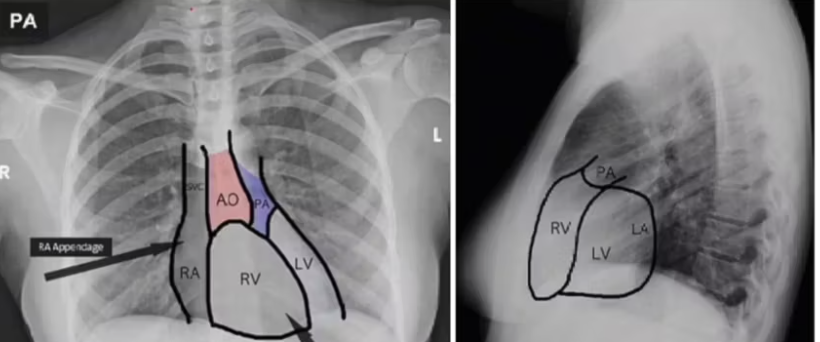

Xray Image

A

stab wounds:

third and fourth intercostal spaces, from the parasternal line to the mid-clavicular line, are most likely to injure ____

Just medial to the mid-clavicular line and further inferiorly (fifth intercostal space)- which ventricle at risk?

Further laterally, past the mediastinal border- which one at risk?

right ventricle

left ventricle

left lung